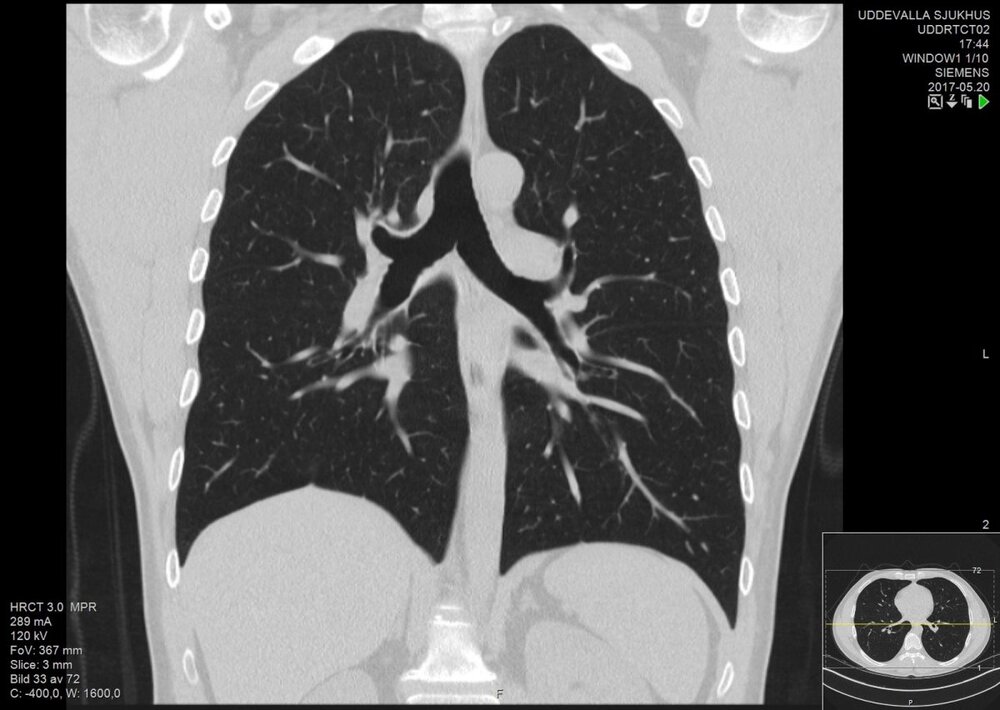

او می‌گوید: «برای پنج روز، بارها سرم زدم و آنتی‌بیوتیک مصرف کردم اما حالم اصلا خوب نشد. روز هشت فروردین حالم به شدت بد شد، به سراغ همان پزشک رفتم و پس از بگومگویی او را قانع کردم تا آرمایش سی‌تی اسکن بدهم و از نتایج آزمایش فهمیدیم من به کرونا مبتلا هستم.»

سرانجام به پیشنهاد یکی از اعضای خانواده، هر ۲۰ نفر آزمایش سی‌تی‌اسکن می‌دهند و نتایج را برای متخصص ریه‌ای در بیمارستان دیگری می‌برند، تا روزهای بحران شروع شود.

پس از بررسی آزمایش‌ها توسط پزشک مشخص می‌شود در دو هفته‌ای که کروناویروس وارد خانه شده بود به جز حسین چهار نفر دیگر هم از آن خانه ۳ طبقه به کروناویروس مبتلا شدند؛ مادر، عمه، شوهر عمه و پسر عمه‌اش. حسین چیز زیادی از آن روزها به یاد ندارد: «پزشک سی‌تی‌ها را با دقت نگاه کرد و سریعا دستور داد که از بین ما ۵ نفری که مبتلا شده بودیم، من، عمه و شوهر عمه‌ام در بیمارستان بستری شویم.»

پدرش اما آن زمان خبر ترسناکی از پزشک شنیده بود که فرد دیگری از آن چیزی نمی‌دانست، او در حالی که اشک می‌ریخت، می‌گوید: «پزشک گفت امیدی به حسین وجود ندارد، چراکه به دلیل تشخیص دیرهنگام بیماری نزدیک ۳۰ تا ۴۰ درصد ریه‌هایش پر از عفونت شده بود.»